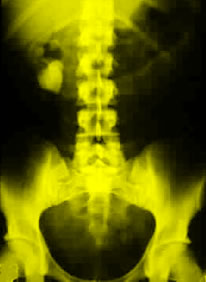

Kidney stones are a major cause of illness, according to background information in the article. The lifetime prevalence of kidney stones is approximately 10 percent in men and 5 percent in women, and more than $2 billion is spent on treatment each year. Researchers believe that larger body size results in increased urinary excretion of calcium and uric acid, thereby increasing the risk for calcium-containing kidney stones. It has been unclear if obesity increases the risk of stone formation, and it has not been known if weight gain influences risk.